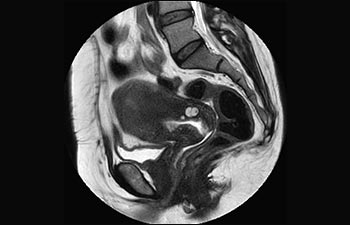

Pelvis

Información general sobre la pelvis femenina